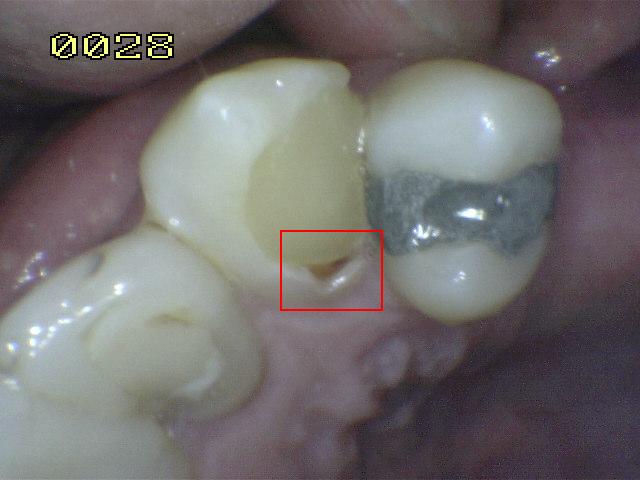

Código 5

(Caries Severa): Cavidad

detectable con dentina visible hasta la mitad de la superficie

-

Cavidad detectable

adyacente a la restauración/sellante con dentina visible

en el espacio de interfase con signos de caries tal como

se describe en el código 4, además de un espacio > 0,5

mm de ancho.

En los casos en que

los márgenes no son visibles, hay evidencia de pérdida

de continuidad en el margen de la restauración/sellante

y en la dentina, detectada por el paso de la punta de

0,5 mm de la sonda cuando se pasa por el margen de la

restauración/sellante.

Criterios para

determinar si la lesión es activa o detenida